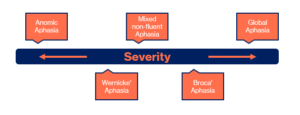

There are a few different types of aphasia, each with their own unique challenges. Here are a few of them:

- Non-fluent Aphasia People with this type know what they want to say but can’t get the words out smoothly. They might speak in short phrases, kind of like texting shorthand — ‘Want water’ instead of ‘I would like a glass of water.’ Reading and writing could be a bit hard too. They can still understand others, though!

- Fluent Aphasia This type is a little different. People with Wernicke’s aphasia can talk easily, but sometimes the words don’t make much sense. It’s like saying ‘couch on the moon’ when they mean ‘let’s go sit outside.’ Understanding others can be tough for them, too and reading and writing might be tricky.

- Global Aphasia This one is more severe. People with global aphasia have lots of trouble with speaking, understanding language and reading and writing. But with support, they can still connect with others through gestures, expressions, and patience.

Different types of aphasia

But remember, aphasia is different for everyone. Some people have trouble with just speaking, others with understanding, and some with both. It can be mild and hardly noticeable or severe resulting in the person not being able to communicate out loud at all.